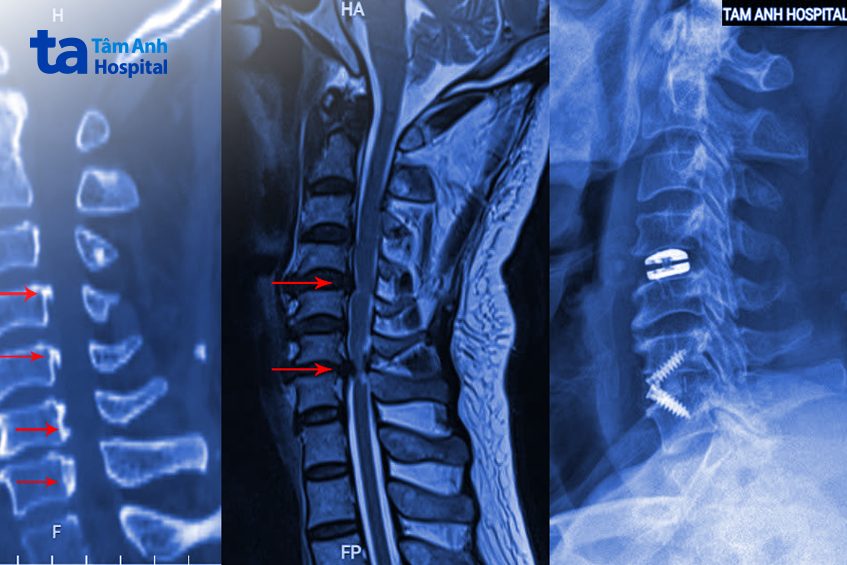

ThS.BS Tạ Ngọc Hà, khoa Chấn thương Chỉnh hình chỉ định bệnh nhân chụp cắt lớp vi tính CT phát hiện tình trạng vôi hóa nhiều đoạn dây chằng dọc sau, là lớp dây chằng có nhiệm vụ giữ vững cột sống, bị canxi hóa và dày lên, làm hẹp ống sống. Chụp cộng hưởng từ MRI phát hiện đĩa đệm C4-5 thoát vị, C6-7 thoát vị nặng, chèn ép tủy cổ nghiêm trọng.

“Tổn thương tủy cổ gây ra tỷ lệ liệt cao trong số các tổn thương cột sống, một khi đã liệt thì khả năng hồi phục rất kém”, bác sĩ Hà cho biết, thêm rằng vôi hóa dây chằng làm cho tổn thương của ông Thức thêm phức tạp, làm hẹp ống sống từ đốt sống cổ C3 đến C7, hiện đã gây yếu liệt tứ chi, nguy cơ liệt vĩnh viễn rất cao nếu không được điều trị ngay lập tức.

Khối thoát vị C4-5 được lấy ra ngoài, đặt đĩa đệm nhân tạo thay thế, đảm bảo bệnh nhân giữ được biên độ vận động cổ sau mổ. Tổn thương đốt sống C6-7 nặng hơn được bác sĩ Hà lấy bỏ đĩa đệm, cục thoát vị chèn ép, giải phóng thần kinh rồi ghép xương nhân tạo và cố định lại bằng miếng ghép đĩa đệm có nẹp vít để tạo độ vững cho toàn bộ cột sống cổ.